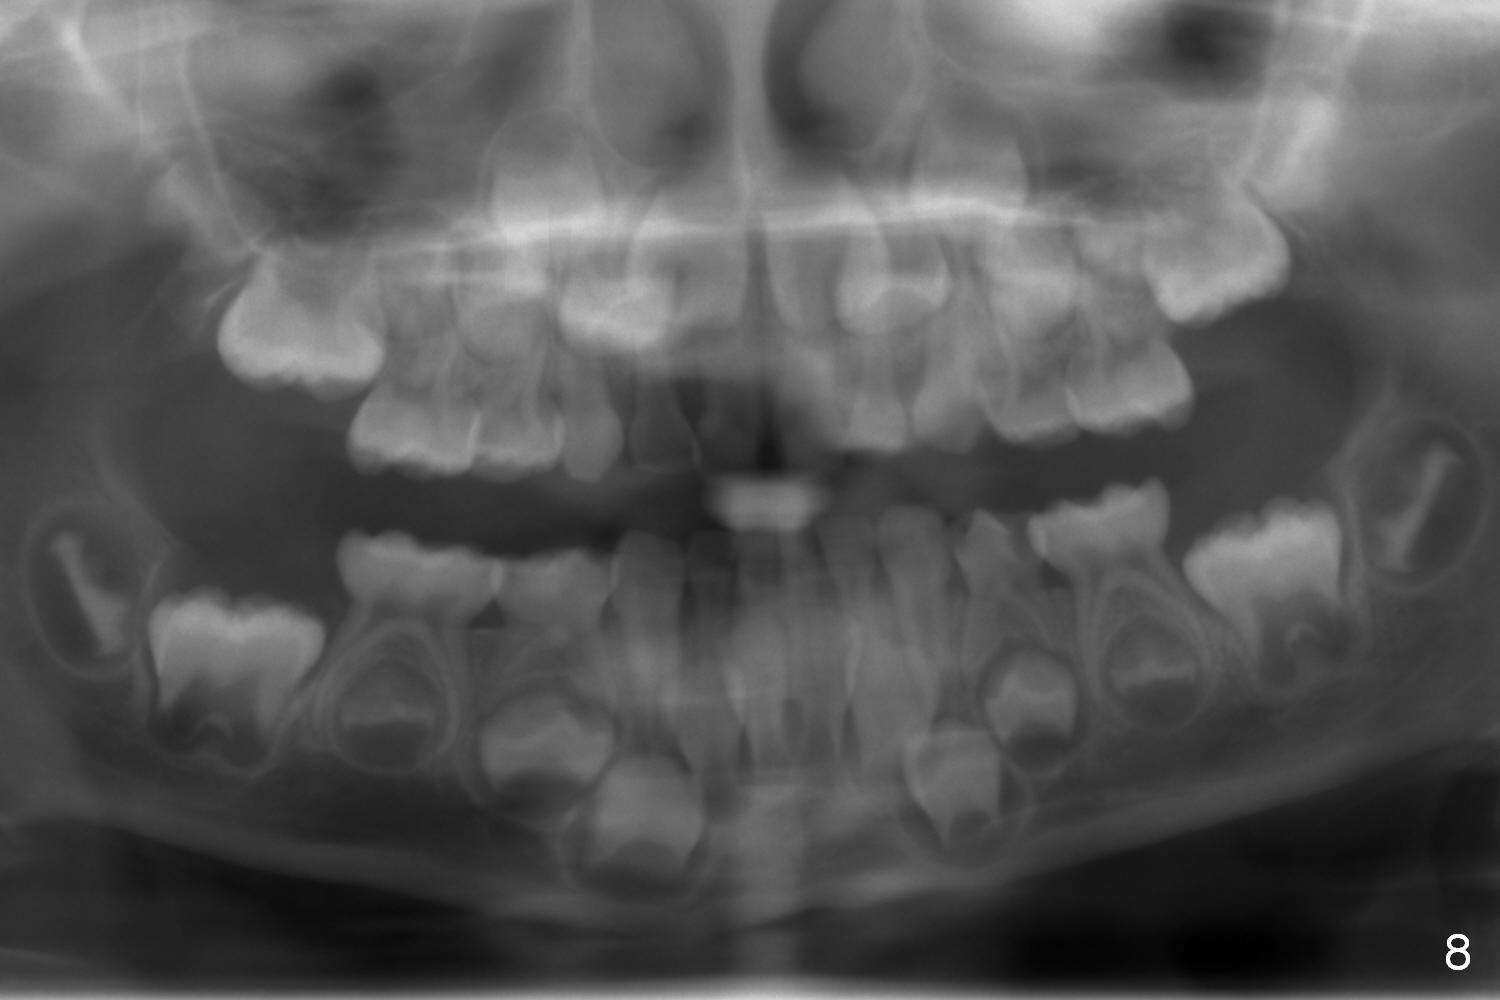

Panoramic X-ray shows underdevelopment of #20 and 29 tooth buds (Fig.6), which is related to K and T being retained (Fig.3). What should be done for K and T as well as 20 and 29?

The patient's mother is 38 years old. She reports that her tooth #20 took long time to erupt. The tooth T remains retained (Fig.7). The patient's 5-year-old sister appears to be normal in tooth bud development (Fig.8).